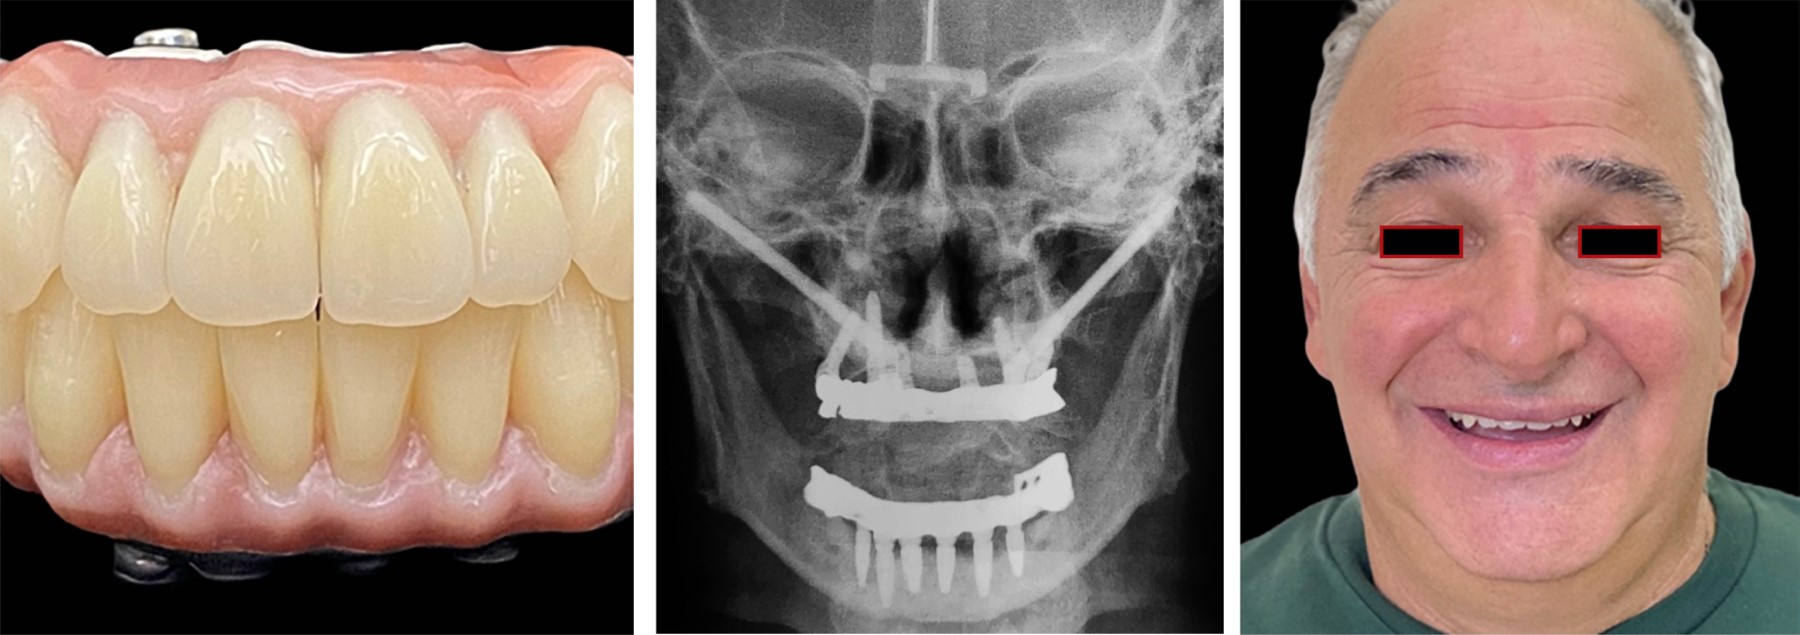

Una vez lograda la osteointegración, se procede a la carga protésica definitiva. En nuestro enfoque de rehabilitación protésica priorizamos la utilización de una barra rígida con componentes protésicos maquinados y revestidos con acrílico termocurado, un material que ofrece ventajas significativas en términos de resistencia y durabilidad, y la incorporación de dientes SR Phonares II de Ivoclar. Esta barra proporciona una base sólida y estable para la prótesis, asegurando una distribución uniforme de las fuerzas masticatorias y una adaptación precisa a la anatomía del paciente. Estudios han demostrado que el acrílico termocurado, como el Ivoclar Vivadent Triplex Hot, presenta una resistencia flexural superior, dando una mayor longevidad de la prótesis (Figura 2).

Se realizó carga diferida con prótesis fija atornillada con base en titanio y revestida con circonio. En el control a los seis meses, se observó recuperación del soporte labial, armonía de los tercios faciales y desaparición de los pliegues periorales (Figuras 9 y 10).

A los dos años, la estabilidad funcional y estética se mantuvo (Figura 11), con mejora significativa en la calidad de vida de la paciente y reinserción social exitosa.

En el plano estético, se observaron mejoras marcadas en la proyección labial, una reducción de pliegues nasogenianos y un perfil armónico del tercio inferior facial, lo cual ha sido evaluado mediante análisis fotográfico pre- y postoperatorio, así como el cuestionario de satisfacción basado en una escala de Likert de 5 puntos, una herramienta común para medir percepciones o actitudes de los pacientes.